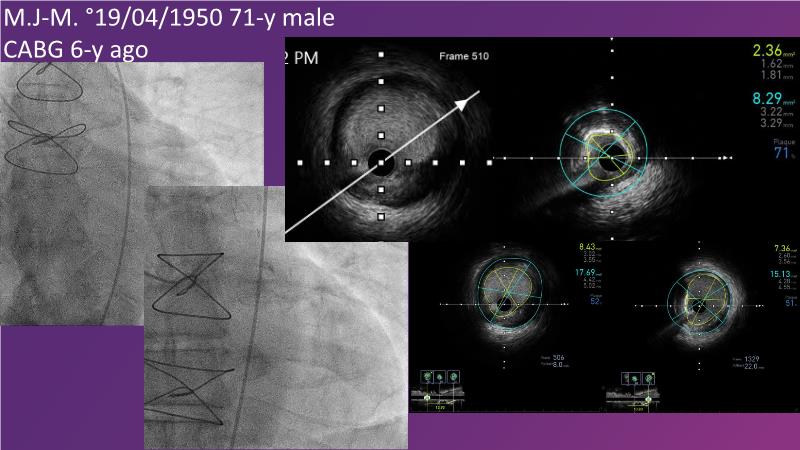

Don't miss this session for expert guidance on preparing and managing complex lesions. Gain insights into choosing the right tools, including microcatheters and balloons, for optimal treatment outcomes. Explore the innovative features of flagship devices for complex PCI, and Pronavi microcatheter and Alveo HP CTO balloon to treat complex CTO lesions. Learn about the safety and efficacy of the Wedge NC scoring balloon, the importance of using POT dedicated balloons in POT and DOT techniques, and get updated tips and tricks from ongoing clinical practices.

- To know the innovative features and capabilities of flagship devices in advancing complex PCI treatment

- To gain insights on Pronavi microcatheter and Alveo HP CTO balloon to treat complex CTO lesions, understand the safety and efficacy of lesion preparation with Wedge NC scoring balloon and the significance of using POT dedicated balloon in POT and DOT technique